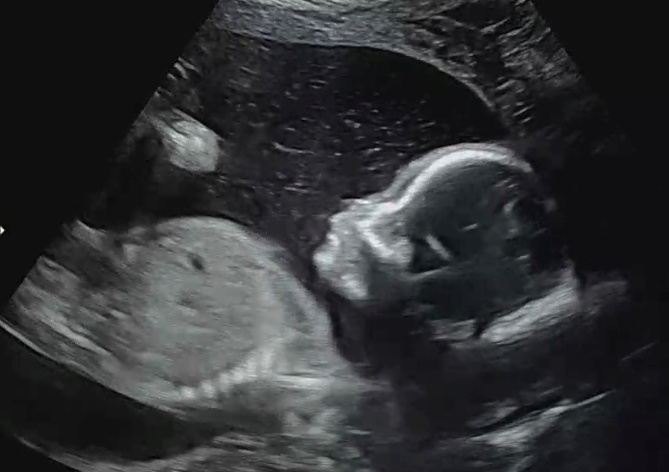

21주 2일 차 - 정밀초음파 예약일

정밀초음파를 보러 병원에 다녀왔다.

뚝딱이가 얼마나 컸을지 그리고 정밀초음파는 괜찮을지 너무너무 궁금했다.ㅎㅎ

정밀초음파는 12분정도 자세히 봐주셨고

뚝딱이가 잘 도와줘서 머리부터 발까지 금방금방 확인했다.ㅎㅎ

선생님께선 정밀초음파는 다 좋아 보인다고 말씀해 주셔서 기분도 좋았다!!